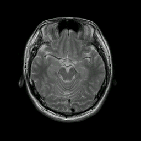

![]() ヘッドフォン無し |

![]() ヘッドフォン有り |